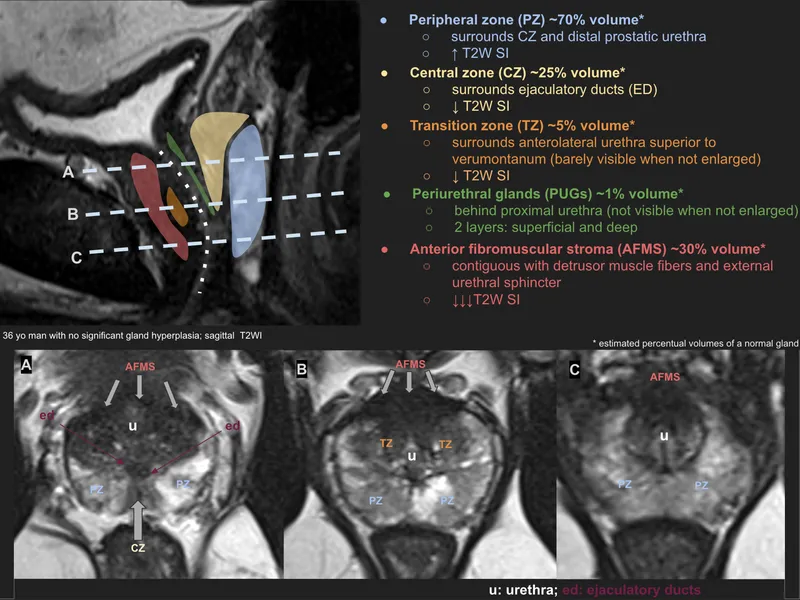

- Zonal Anatomy (T2W MRI):

- Peripheral Zone (PZ): ~70% cancers. High T2 signal.

- Transition Zone (TZ): BPH origin. Heterogeneous T2 signal.

- Central Zone (CZ): Low T2 signal.

- Anterior Fibromuscular Stroma (AFMS): Very low T2 signal.